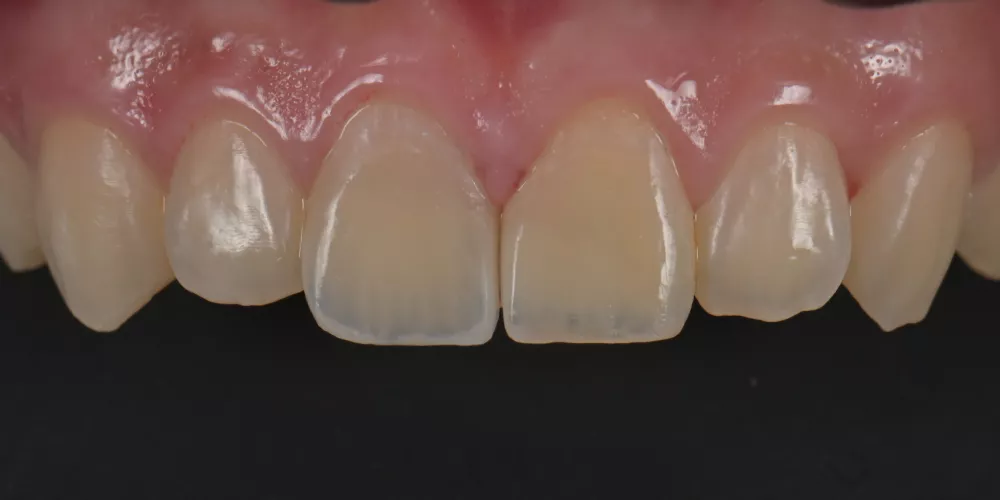

因此,每一次的治療,我都傾注最大的心力,在品質及細節上堅守高標準,讓成果真正經得起考驗。

一副笑容的改變,帶來的不只是外觀的提升,更深刻影響一個人在職場、人際與生活中的自信。相反的,一顆做得不夠好、撐不久的牙齒,或許短期內無痛無礙,卻會在無形中逐漸消磨一個人對生活的底氣。